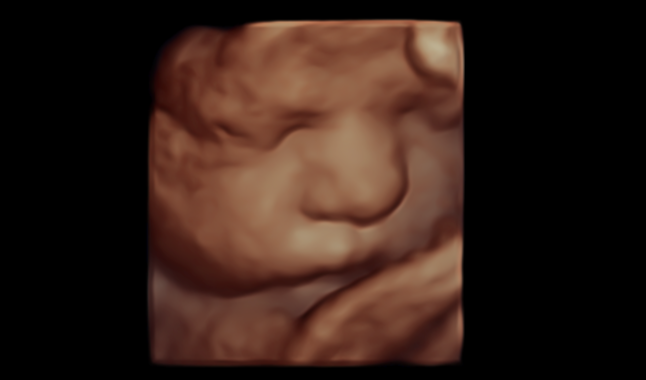

What is 3D/4D Imaging?

1

3D and 4D ultrasound are advanced imaging techniques that allow you to see detailed, three-dimensional images of your baby. 3D imaging produces a still, lifelike image, while 4D adds the element of real-time movement — so you may see your baby yawning, stretching, or even smiling.

Our Expertise

2

At Central West Women’s Imaging, 3D/4D imaging is available for all women as part of our routine obstetric assessment. This is part of our commitment to providing the highest standard of obstetric ultrasound in regional New South Wales. Our sonographers are experienced experts in 3D/4D imaging techniques and use dedicated GE women’s imaging equipment optimised for this purpose.

While we are committed to giving you the best possible experience, we are unable to guarantee a particular 3D/4D image, as this depends on your baby’s position and the amount of fluid around them on the day. Our first priority is always a thorough, high-quality diagnostic ultrasound — we will do all we can within your appointment time to also capture 3D/4D images for you.